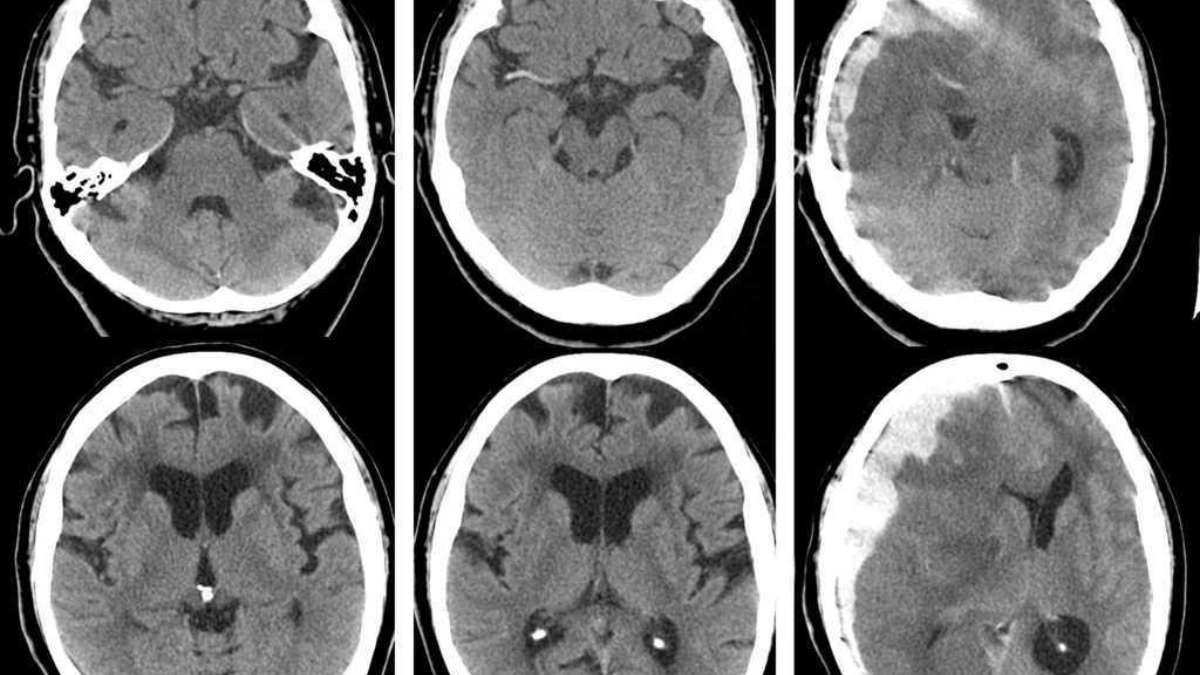

Hematoma subdural: definição, causas, sintomas, tratamento, diagnóstico, evolução e possíveis complicações - O hematoma é uma coleção sanguínea resultante de uma hemorragia (extravasamento de sangue) nos espaços meníngeos, entre a aracnoide e a dura-máter (abaixo da dura-máter; subdural). Para melhor entender o que ocorre, deve-se lembrar de que há um espaço virtual entre as.. 4. Idade avançada: O envelhecimento dos vasos sanguíneos pode torná-los mais frágeis e propensos a rompimentos, aumentando o risco de hematomas subdurais em pessoas idosas. Sintomas do Hematoma Subdural. Os sintomas de um hematoma subdural podem variar dependendo da gravidade e da localização do sangramento.

Declara, outrossim, que o(a) referido(a) médico(a), atendendo ao disposto nos artigos 31 e 34 do Código de Ética Médica e no artigo 9o da Lei 8.078/90 e após a apresentação de métodos alternativos, sugeriu o tratamento médico cirúrgico de TRATAMENTO CIRURGICO DO HEMATOMA SUBDURAL CRÔNICO, antes apontado, apresentando informações.. O hematoma subdural tem evolução variável, a depender do tamanho do hematoma, da idade do paciente, dos sinais/sintomas neurológicos à apresentação, da presença de coagulopatia ou neoplasia subjacentes e de lesões associadas. Deve-se considerar a terapia profilática de uma semana com antiepilépti.